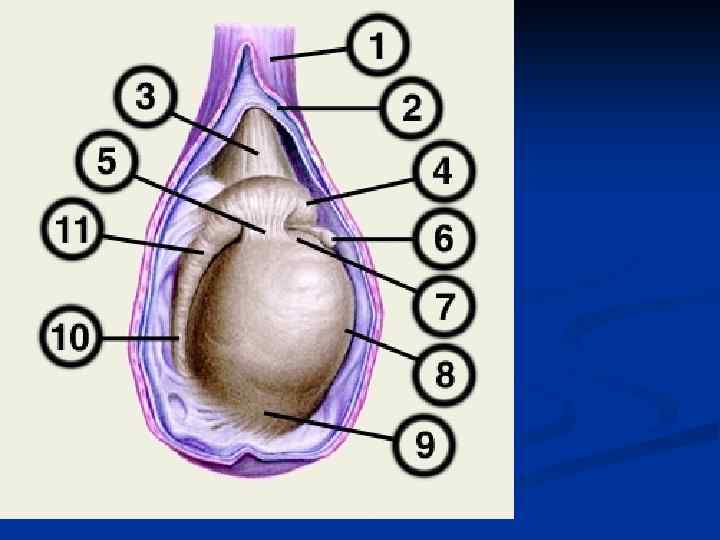

Мошонка, scrotum – выпячивание передней брюшной стенки с 2 камерами для яичек (мужских половых желез). Покрыта тонкой, пигментированной кожей, имеющей складки и волосяной покров. По передней срединной линии проходит шов мошонки, raphe scroti.

Мошонка, scrotum – выпячивание передней брюшной стенки с 2 камерами для яичек (мужских половых желез). Покрыта тонкой, пигментированной кожей, имеющей складки и волосяной покров. По передней срединной линии проходит шов мошонки, raphe scroti.

В мошонке выделяют 7 слоев (оболочек), или оболочек яичка: 1. Кожа, cutis (1) 2. Мясистая оболочка, tunica dartos (14); 3. Наружная семенная фасция, fascia spermatica externa (20); 4. Фасция мышцы, поднимающей яичко, fascia cremasterica (11); 5. Мышца, поднимающая яичко, musculus cremaster (12); 6. Внутренняя семенная фасция, fascia spermatica interna (13); 7. Влагалищная оболочка яичка, tunica vaginalis testis (18 — висцеральная пластинка; 19 — париетальная пластинка);

В мошонке выделяют 7 слоев (оболочек), или оболочек яичка: 1. Кожа, cutis (1) 2. Мясистая оболочка, tunica dartos (14); 3. Наружная семенная фасция, fascia spermatica externa (20); 4. Фасция мышцы, поднимающей яичко, fascia cremasterica (11); 5. Мышца, поднимающая яичко, musculus cremaster (12); 6. Внутренняя семенная фасция, fascia spermatica interna (13); 7. Влагалищная оболочка яичка, tunica vaginalis testis (18 — висцеральная пластинка; 19 — париетальная пластинка);